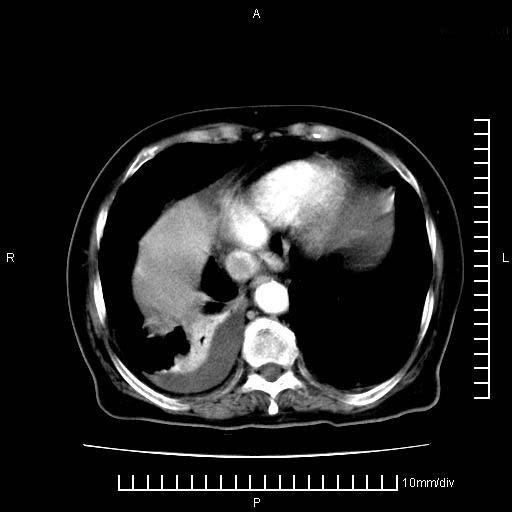

标题: CT28280:腹部增强:女性,80岁

上腹疼痛月余,外院核磁诊断胰腺癌。现临床示右下腹可明显触及包块,可片子上怎么没有看到?

3。右胸腔积液,伴右肺下叶部分萎陷。

1)考虑胰腺癌并胰腺假性囊肿形成。2)肝内低密度灶,不排除转移。3)右肾盂积水。4)腹水。5)右侧胸腔积液并右肺下叶部分膨胀不全。

考虑胰腺ca伴腹膜腔转移、肝左叶转移、右肾积水。右胸腔积液。

考虑胰腺ca伴腹膜腔转移、肝左叶转移、右肾积水。右胸腔积液。支持